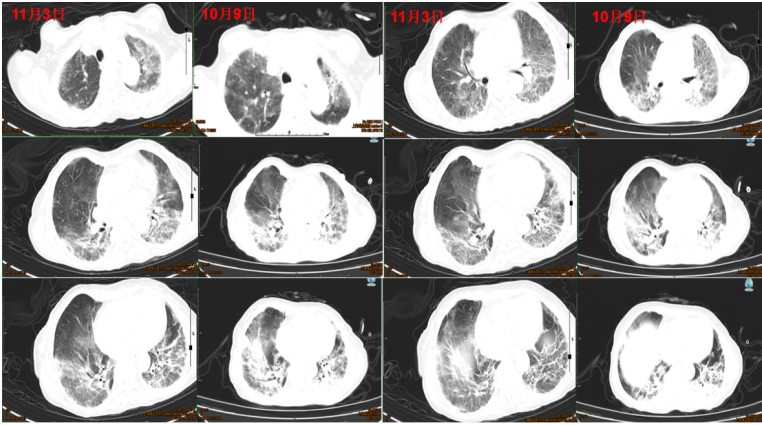

• 胸部CT(9月27日):两肺间质性肺炎改变(图7)

图片

图7  患者入院胸部CT

复查胸部CT可见病灶明显吸收(图8)

图8  患者治疗前后胸部CT比较